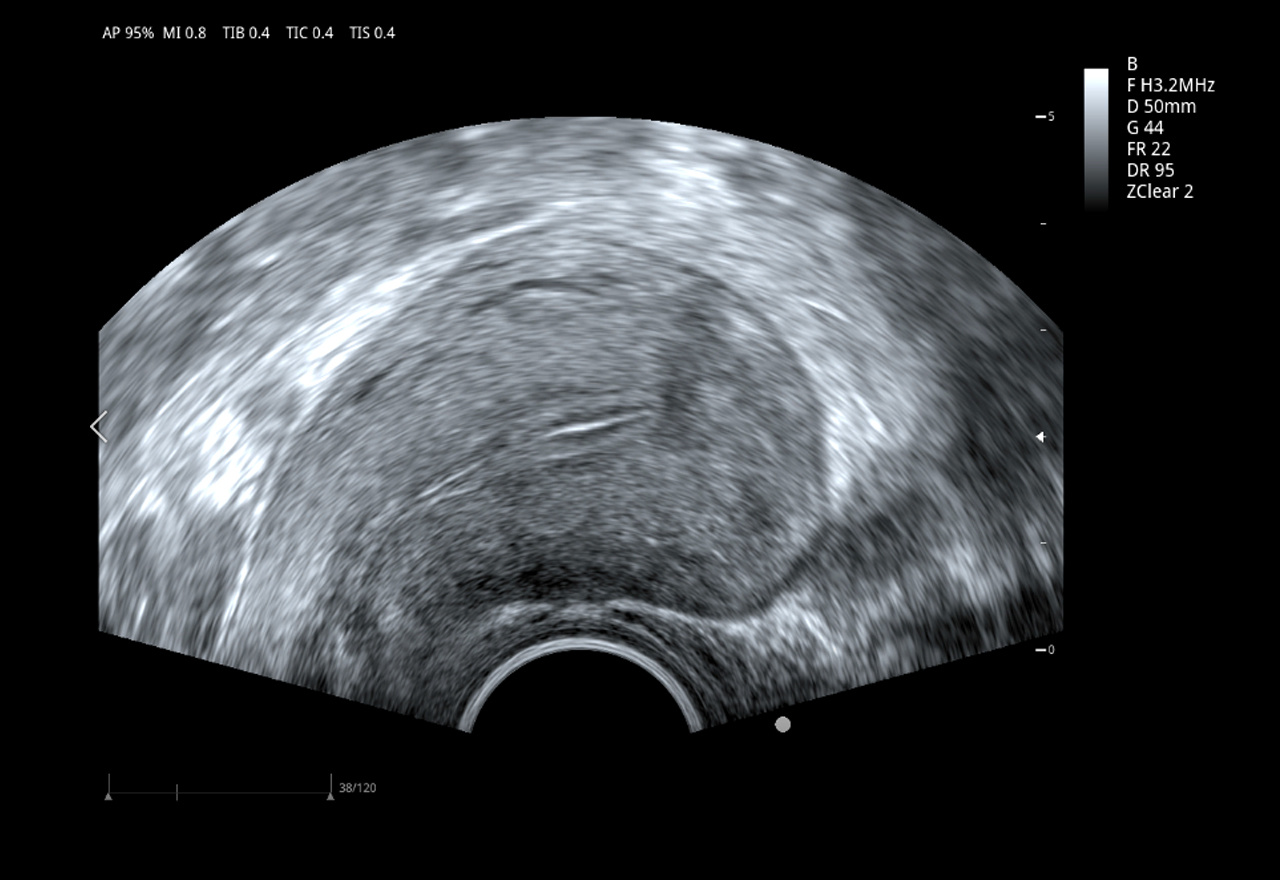

Трансвагинальный датчик 6E1PD

• Рабочая полоса частот: 2,5–13,0 МГц

• Количество элементов: 128

• Радиус кривизны: 10 мм

• Применение: акушерство и гинекология, диагностика предстательной железы, исследования тазового дна.